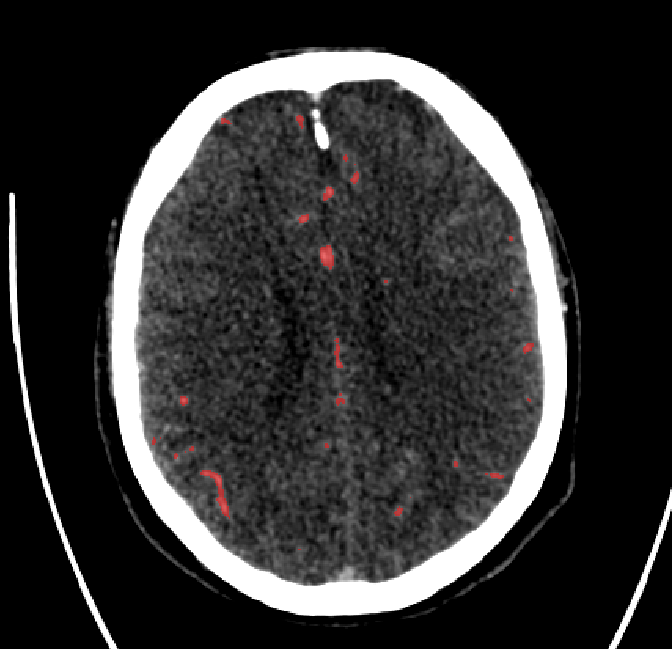

After fine-tuning, the two pre-train conditions appear to have little or no difference in terms of qualitative performance at the vessel segmentation task. However, when compared to the models trained only on real data, there are noticeable differences. Throughout Figures 4.3-4.9, the model pre-trained on scans with original CT noise is to be taken as representative of segmentation performed by the Perlin noise pre-training condition. Images showing the hand-labeled ground truth, as well as the unlabeled slice, are presented for comparison.

Refer to caption

Figure 4.7: Segmentations on regions near the top of the skull. Unaltered image (left). No pretrain model (mid-left). Fine-tuned model (mid-right). Hand-labeled ground truth (right).

Figure 4.8: Side view of segmentations on regions near the left side of the skull. Unaltered image (left). No pretrain model (mid-left). Fine-tuned model (mid-right). Hand-labeled ground truth (right).

For vessels in the center of the head, all model types appear to accurately segment vessels. In certain cases, the models appear to learn to correctly avoid segmenting pieces of bone that could, in terms of shape and contrast, easily be confused with large vessels. An example of this can be seen in the frontal section of Figure 4.6.

The models appear to have a hard time segmenting vessels close to the skull surface. The model trained exclusively on patient data appears to struggle far more for these types on conditions than the fine-tuned models. Figure 4.8 shows an example of the fine-tuneds model having close to no trouble segmenting vessels near the left side of the skull, while the baseline model suffers heavily from false negatives. To lesser degree, this effect can also be observed in the frontal lobe of Figure 4.9 In the other hand, Figure 4.7 presents an example of both models failing to segment vessels near the top of the skull.

In the other hand, it should be noted that fine-tuned models suffered from false positives more often than models with no pre-training. The fine-tuned models appeared to occasionally segment regions near the skull, which although similar in intensity to vessels, had no resemblance in terms of shape. Examples of this are seen in Figure 4.4 near the occipital bone and near the right temporal bone. Examples of oversegmentation were observed to happen commonly around the internal carotid arteries. This is likely due to the amount of contact surface between the artery and the surrounding bone. There was also a tendency for all model conditions to segment bone regions that were similar in shape to large vessels (Figures 4.3 and 4.4). Bone structures in such regions have similar pixel intensities to the arteries transporting contrast material, which could explain the source of confusion for a model.